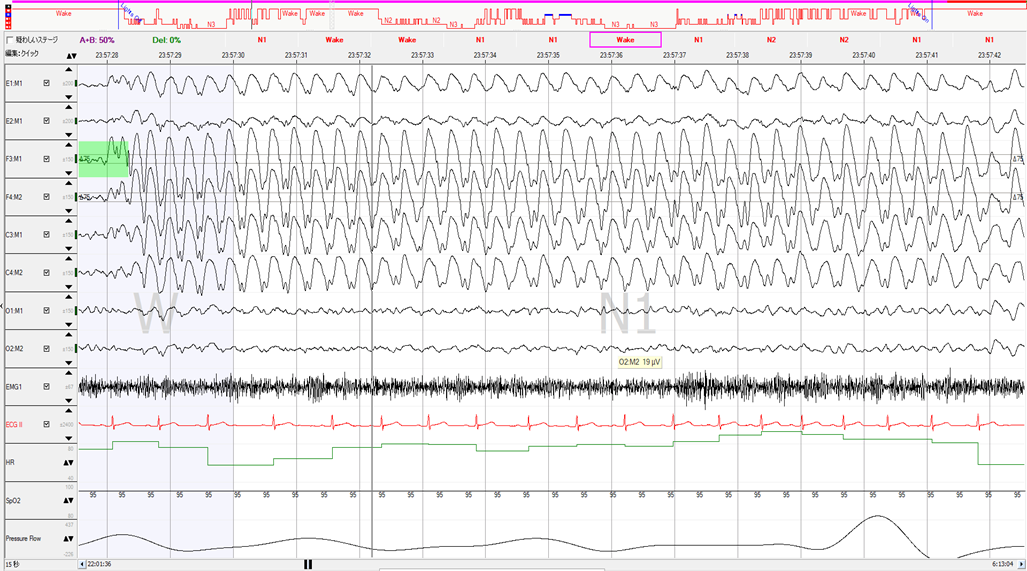

体位と呼吸イベントの関係性が説明できない症例

30歳台 男性 身長:167㎝ 体重:71kg BMI:25.5 ESS:19 咳喘息で通院中、無呼吸やいびきの指摘もあり、簡易検査を施行しました。REI=16/時間、最低SpO2=86%、2%ODIが高値だったことで、PSG精査となりました。PSG結果はAHI=51.2回/時間と高値になりました。深睡眠も記録されていますが、AHIが高値となったのは、呼吸イ…